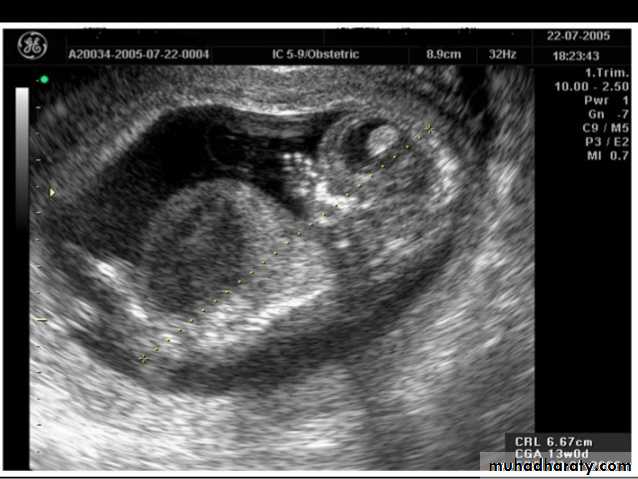

US of the obstetric & Gyne.BPD together with head circumference (HC), abdominal circumference (AC), and femur length (FL) are computed to produce an estimate of fetal weight. In the second trimester this may be extrapolated to an estimate of gestational age and an estimated due date (EDD) .